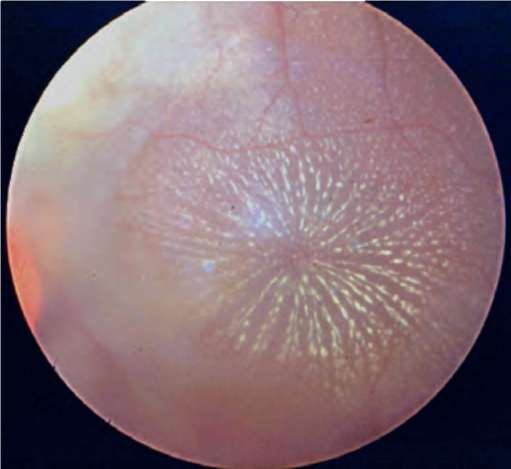

Рис. 26.1. Центральный токсоплазмозный хориоретинит